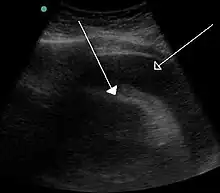

Echocardiogram (ultrasound): when pericardial effusion is suspected, echocardiography usually confirms the diagnosis and allows assessment of the size, location and signs of hemodynamic instability.[4] A transthoracic echocardiogram (TTE) is usually sufficient to evaluate pericardial effusion and it may also help distinguish pericardial effusion from pleural effusion and MI. Most pericardial effusions appear as an anechoic area (black or without an echo) between the visceral and the parietal membrane.[1] Complex or malignant effusions are more heterogeneous in appearance, meaning they may have variations in echo on ultrasound.[5] TTE can also differentiate pericardial effusion based on the size. Although it's difficult to define size classifications because they vary with institutions, most commonly they are as follows: small <10, moderate 10–20, large >20.[5] An echocardiogram is urgently needed for evaluation when there is concern for hemodynamic compromise, a rapidly developing effusion or history of recent cardiac surgery/procedures.[1]

A large anechoic (black) pericardial effusion as seen on ultrasound. Closed arrow: the heart, open arrow: the effusion